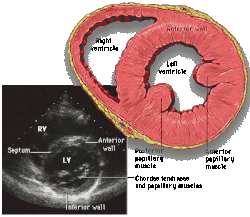

![]() Parasternal short axis |

Each figure contains a TTE with a black background, and a corresponding colored illustration. | Patrick J. Lynch and C. Carl Jaffe, Yale University, 2006. | ||||||||||

Click on a figure to enlarge it and see some parts of the heart identified. RV, right ventricle; LV, left ventricle; RA, right atrium; LA, left atrium; TV, tricuspid valve; MV, mitral valve; AV, aortic valve; RVOT, right ventricular outflow tract; LVOT, left ventricular outflow tract |